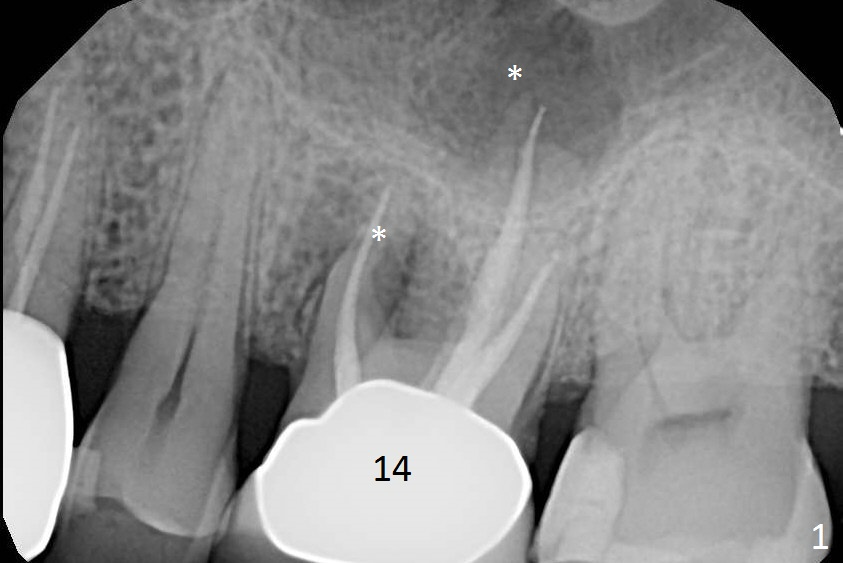

A 70-year-old man will return for #14 extraction and implant placement after consultation with an endodontist (Fig.1). Note the large periapical radiolucencies associated with the mesiobuccal and palatal roots (*). After extraction and Metronidazole, start osteotomy in the septum, place PRF membranes/plug and allograft/Osteogen and then a dummy implant or tap. Place a large definitive implant (Fig.2 green) higher than the sinus floor (red), but lower than the palatal apex (purple).